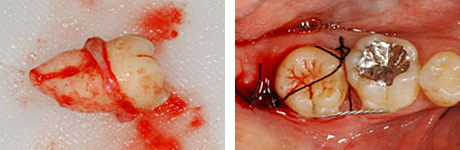

移植のために抜歯された右下の親知らず。歯根がまだ完成していない若い歯です。

移植直後

移植直後。歯根がまだ完成していない歯では、根の先が開いていることに気づきます。